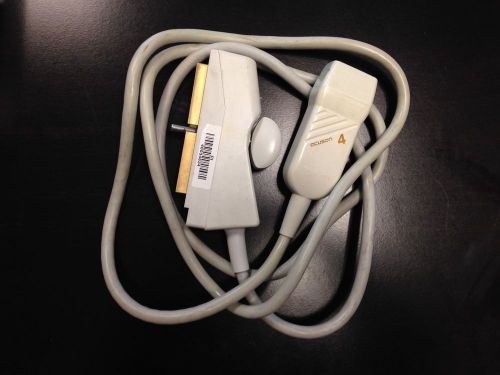

ACUSON V4 Ultrasound Needle Guide Transducer Probe-sn: 40032227

ACUSON V4 ULTRASOUND NEEDLE GUIDE TRANSDUCER PROBE-SN:40032227

ACUSON V4 Ultrasound Needle Guide Transducer Probe-sn: 40024548